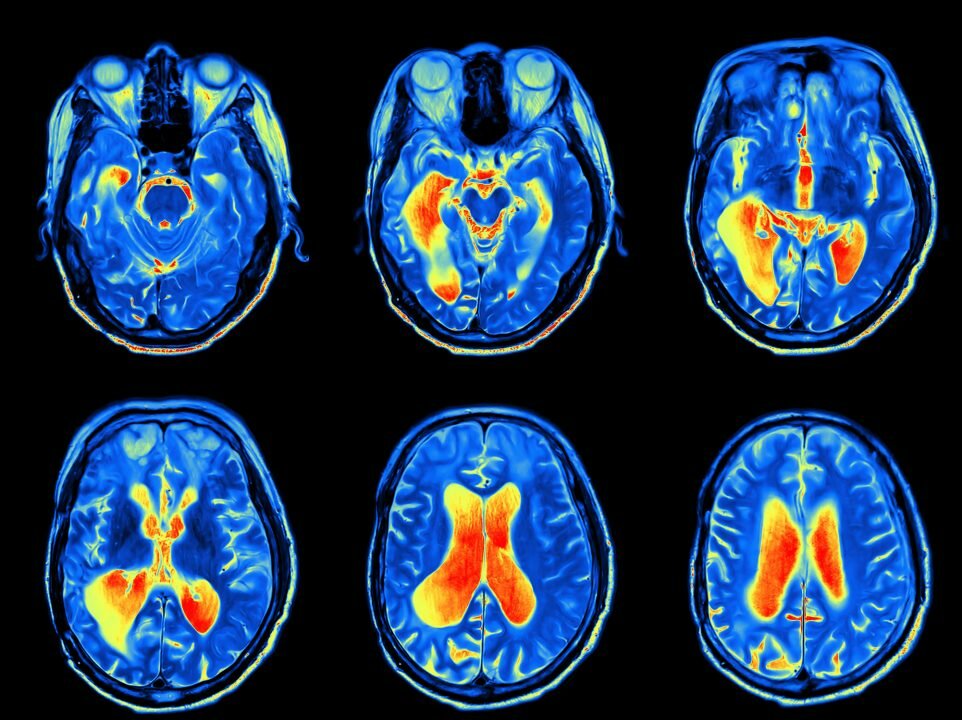

There’s a lot we know (and don’t know) about the unique aspects of the female brain, so the lack of female-specific research is a real issue for women’s health.

Science tells us that female and male brains are different yet biomedical research is largely conducted on males, as if they’re a neutral stand-in for the human population as a whole.

The problem is, female brains can have starkly different neuroimmune responses from males. And our lack of basic understanding is having a very real impact on women and their health.

The female brain is remarkably dynamic, responding uniquely to the early life environment, aging and various life stages in between.